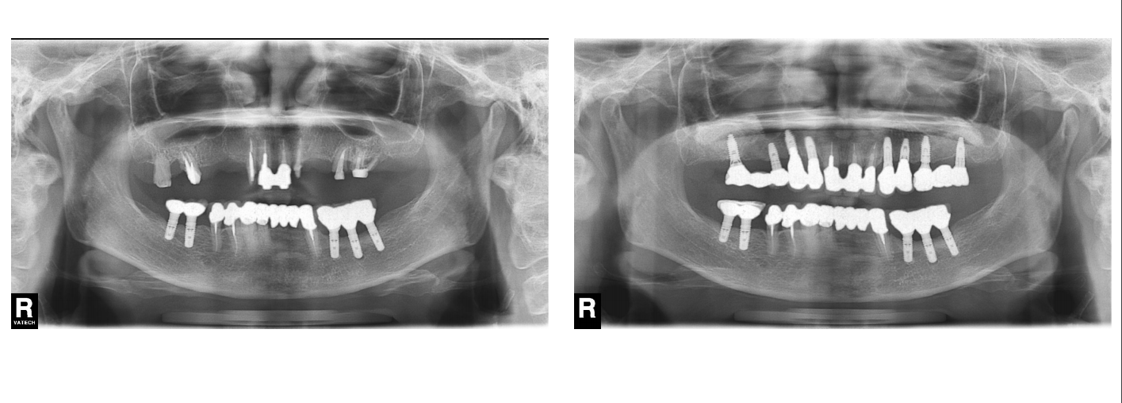

インプラント治療の症例5

(歯が1本もない・インプラントで入れ歯を支える)

治療前

治療後

| 診断名・主訴 | ①歯茎が腫れる ②入れ歯を作りたい |

| 年齢 | 72歳 |

| 治療期間 | 1年間 |

| 治療内容 | インプラント義歯治療 |

| 治療に用いた主な材料、設備機器 | 京セラFINESIAインプラント 上部構造:義歯 |

| 抜歯部位 | 下顎 |

| 治療費 | 約200万 |

| リスク・副作用 | 術後出血や腫れ |